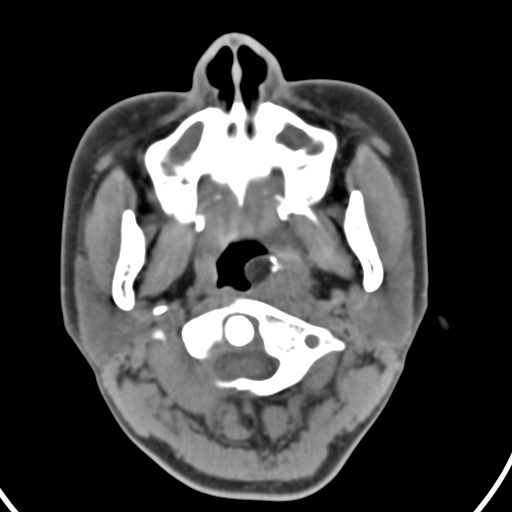

以下是引用zjzjr在2008-12-5 11:46:00的发言:[br]脂肪密度,壁有钙化.考虑口咽部皮样囊肿可能性大.双侧上颌窦炎,双侧下鼻甲粘膜肥厚.增殖腺肥大,扁桃体亦增大,考虑炎性.

以下是引用随光逐影在2008-12-5 18:27:00的发言:[br]1)考虑左侧茎突过长综合征并茎突舌骨韧带囊肿形成突入咽部;左侧咽部慢性炎症。2)鼻咽腺样体肥大。3)双侧扁桃体肿大。4)双侧上颌窦炎。5)双侧下鼻甲粘膜肥厚。